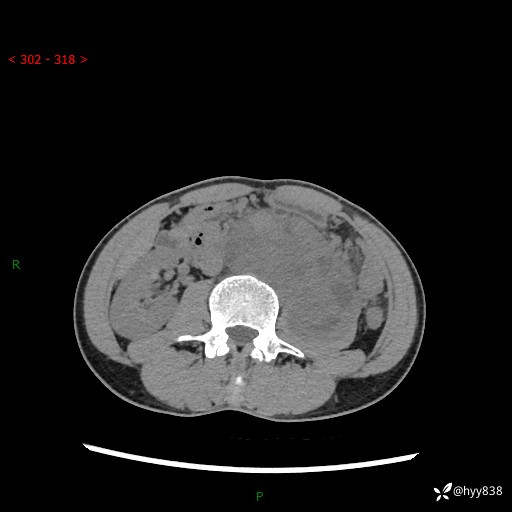

简要病史:患者无明显诱因出现左侧下腹及左侧腰背部疼痛,为间歇性隐痛,我院行胃肠镜检查,提示慢性非萎缩性胃炎,予以口服药物治疗,效果欠佳,后仍觉腹痛不适,遂至当地中医医院就诊,行彩超提示左肾积水及左肾实质性占位,遂来我院泌尿外科就诊

腹部CT平扫+增强